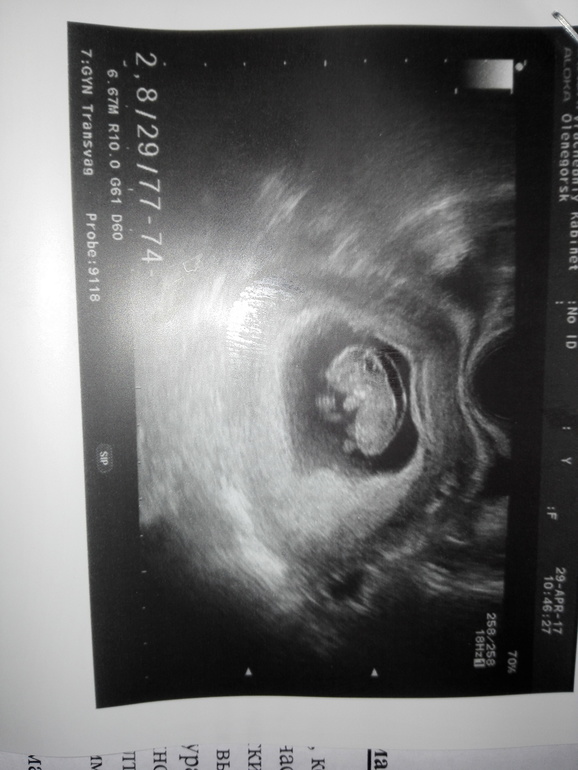

Продолжение... я 5 мая на прием к гинекологу отправилась, зашла и говорю была на УЗИ намерели ТВП 2,8 мм. Гинеколог мне сразу: сохраняем или сразу направление на анализы на аборт? Я скажем так не много офигела, конечно сохраняем, надо хоть анализы сначала сдать. Правда сказали дадут направление на скрининг, звонить узнавать. Сегодня 7 мая была на УЗИ у другого специалиста, аппарат УЗИ более высокого класса. Врач сразу сказал,какой умный вам ТВП мерил на таком сроке? Итог: Срок 11,1 недель,твп 0,8 мм,кости носа лоцируются все отлично и никакого расширения ТВП вообще нет.Малышок нас активничал,ручками и ножками махал. Вот тебе и опытный специалист,такую мне ерунду на первом УЗИ наговорил,всю неделю переживала.

Кстати и подросли мы КТР 47 мм.

правильно вам написали, что минимальный размер КТР=45мм для проведения скрининга и измерения ТВП!!! У меня подруге так одна умелица в 9 недель ТВП намерила и отправила на аборт! Хорошо переделала через пару недель и все было в норме.

ТВП на таком сроке не измеряют, с 11 по 13 неделю, на скрининге. при ктр от 45 мм.

Рановато вам твп намерели.сейчас это не информативно,не зря именно в 12-14 делают скрининг.там сразу и кровь на трисомии возьмут и точно все замерят. Ну обычно смотрят сердцебиение и ктр на таком сроке. Не накручивайте.а вот у брата жены тоже твп был завышен немного но кровь хорошая,носик был и дитя здоровое родила)))